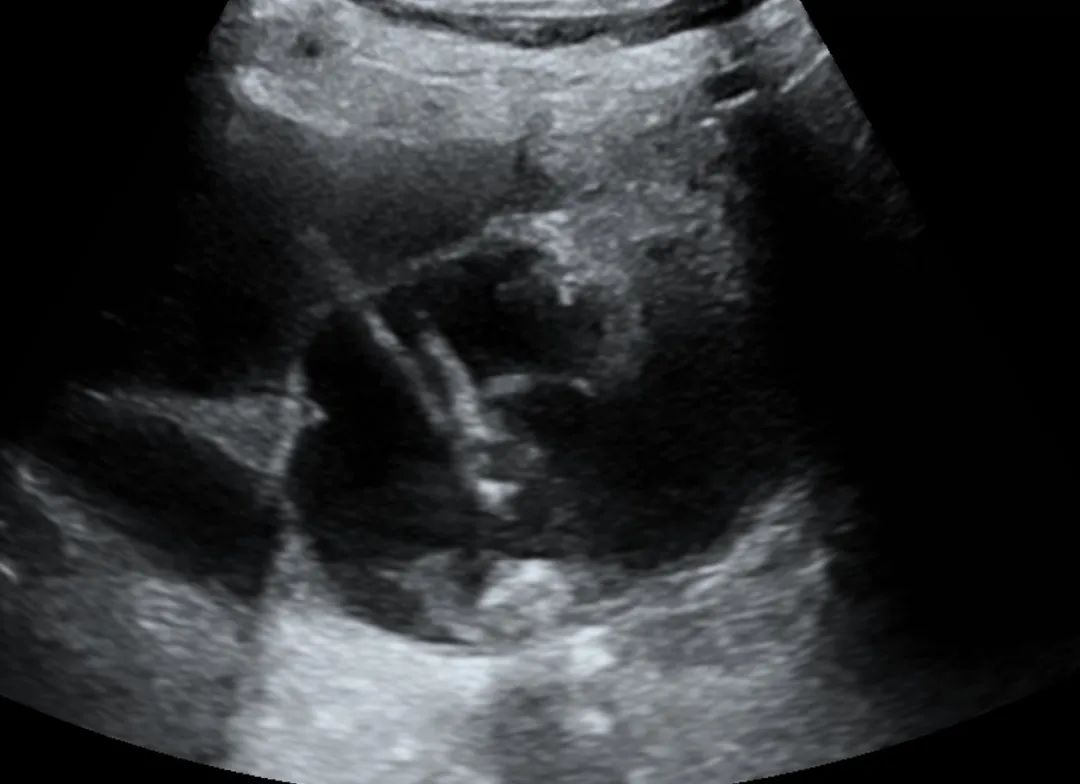

虽然困难重重,但为了患者的一线生机,在充分评估患者条件和进针安全路径的情况下,再次与患者家属谈话,告知所有出血、胆瘘等并发症可能出现的情况后,在家属的同意下,超声介入医师顶着压力为患者进行了床旁超声引导下胆囊穿刺置管引流术。

在超声介入医生准确的评估、完善的路径规划和娴熟的操作下,局麻——进针——减压——导丝——扩皮——置管——固定,一步步操作,按部就班、娴熟流畅、有条不紊的进行着,全程监控,避开血管,一次成功,安全顺利的完成了置管,即刻引流出草绿色胆汁50ml,经评估置管通畅,患者胆囊的危象得到了缓解,有效控制了胆囊肿大及胆管扩张带来的危险,给临床心梗对症处理及抗炎治疗赢得了时间。